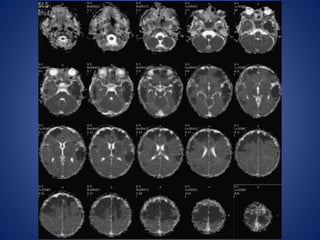

5 yrs male child with history of left sided focal seizures with secondary generalization

5 yrs malechild with history of left sided focal seizures with secondary generalization